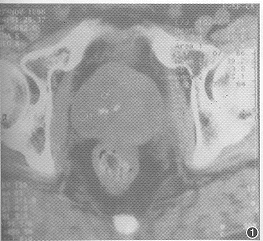

前列腺恶性黑色素瘤一例

恶性黑色素瘤占原发恶性肿瘤的1% ......